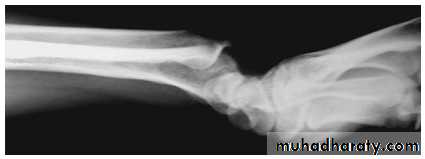

Lateral radiograph

Radial club hand

Partial or complete absence of the radius with radial deviation of the hand.

May be associated with other congenital anomalies or blood dyscrasias (eg thrombocytopenia).

Treated by serial manipulation and casting then surgical correction.